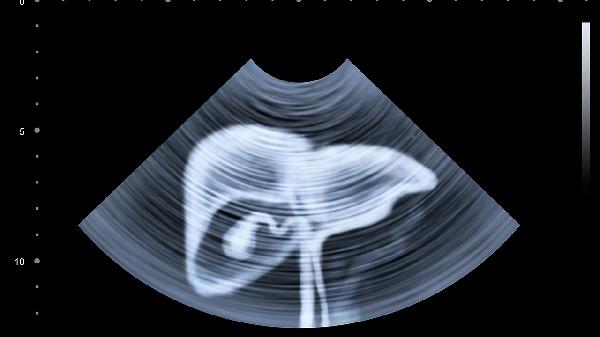

尿路梗阻可能导致脓液积聚,伴随会阴部胀痛。超声引导下穿刺引流可清除脓液,需配合静脉注射抗生素防止感染扩散。

治疗期间应卧床休息,清淡饮食,定期复查超声评估恢复情况,出现排尿灼痛或发热加重需及时就医。